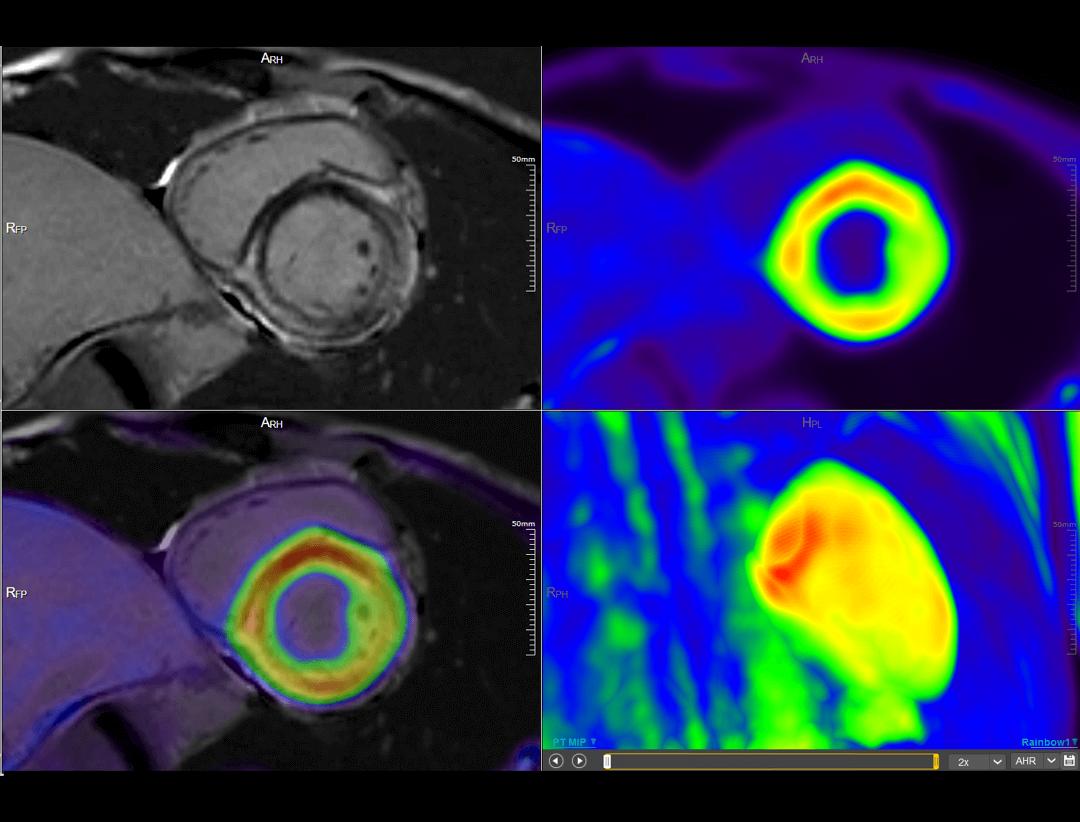

uSync Research deschide noi perspective în cercetarea PET/MR prin codificarea simultană a secvențelor RMN, a datelor PET list-mode și a informațiilor fiziologice într-un flux unic sincronizat spațiu–timp. Această integrare oferă oportunități avansate pentru urmărirea în paralel a radiotrasorilor PET și MR, realizarea simultană a examinărilor cardiace PET și RMN, explorarea funcțională în neurologie și dezvoltarea radiomicii multi-parametrice, ducând cercetarea imagistică la un nou nivel.

uPMR 790 permite imagistică simultană PET/MRI cu rezoluție temporală și spațială ridicată. Această tehnologie redefinește standardele clinice și de cercetare, oferind imagini anatomice și funcționale în timp real.